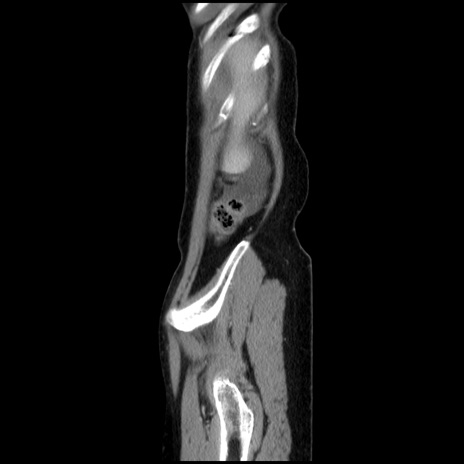

症例32(矢状断像)

【症例】40歳代 女性

【主訴】上腹部痛、嘔気・嘔吐

【現病歴】約9時間前頃から急に上腹部痛、嘔気、嘔吐が出現。改善しないため救急要請。

【既往歴】子宮頚癌(広汎子宮全摘術、放射線療法)、腸閉塞

【身体所見】腹部:平坦、軟、腸雑音亢進、上腹部を中心に腹部全体に圧痛あり。

【データ】WBC 8400、CRP 0.03